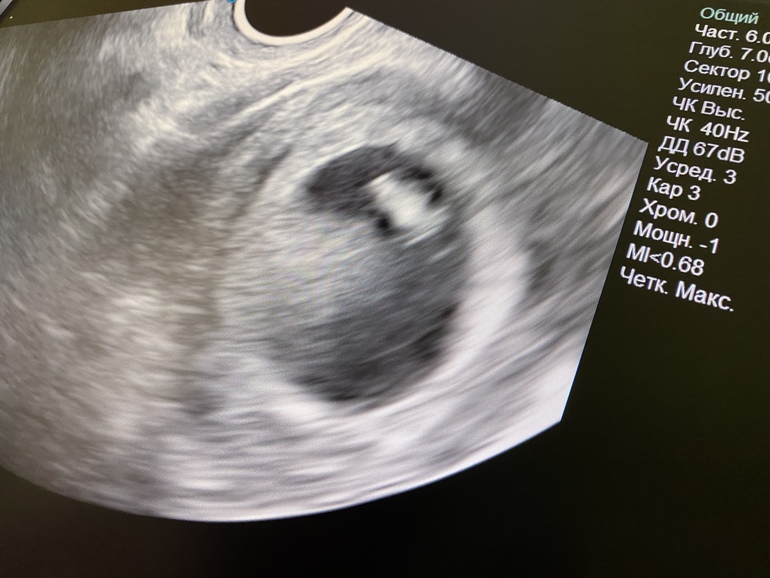

Через неделю на узи вот такой вот 6-и недельный человек 😻